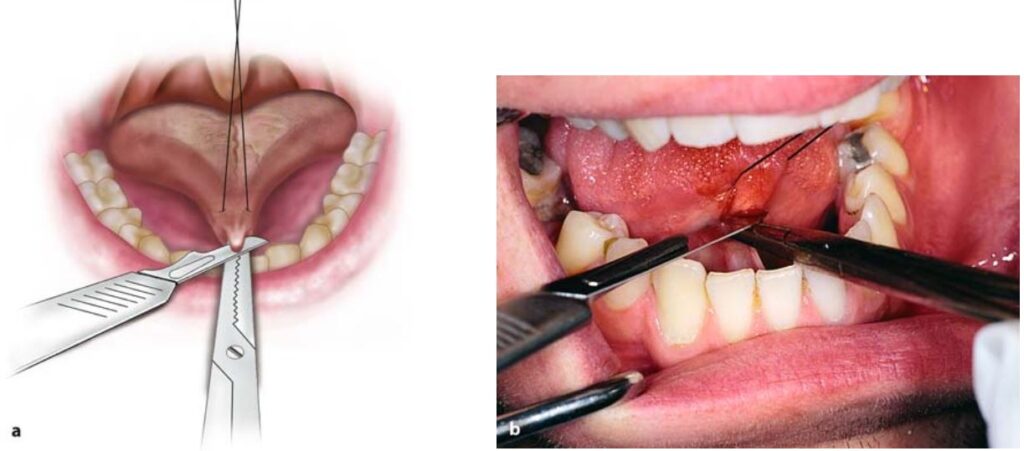

Sau khi gây tê thì lưỡi được kéo lên trên và lui sau bằng một mũi khâu xuyên qua đầu lưỡi.

Sau đó dùng một cây kẹp cầm máu thẳng, kẹp vào khoảng 1/3 giữa theo chiều dọc của thắng, song song với sàn miệng (H10.83).

Thực hiện rạch theo kẹp cầm máu, đầu tiên là rạch ở phía trên, sau đó đến phía dưới kẹp (H10.84, 10.85).